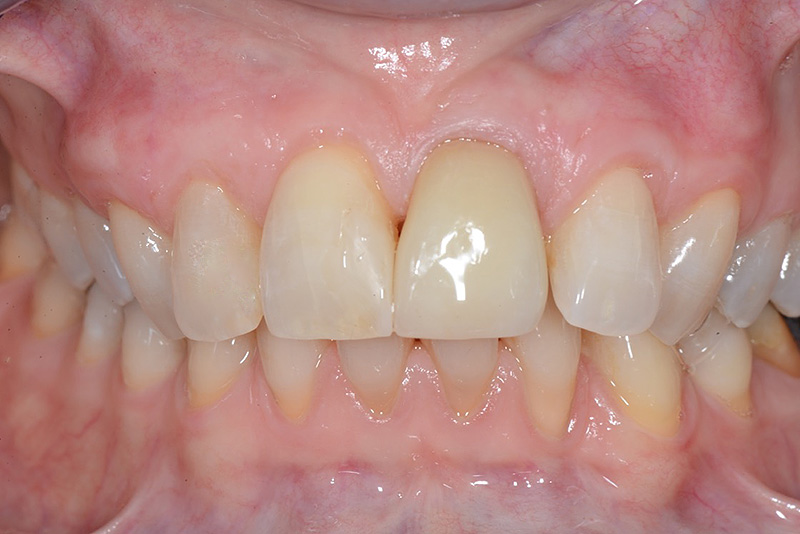

Vengono utilizzati 2 tipi di provvisori: il primo, cementato ai denti vicini, viene utilizzato dal momento dell’estrazione del dente fino ad impianto osteointegrato (circa 6 mesi); il secondo, avvitato direttamente all’impianto, ha una funzione di prova estetica ma soprattutto di guida per la maturazione dei tessuti gengivali peri-implantari portandoli verso la maturazione completa prima di posizionare la corona finale in disilicato di litio.